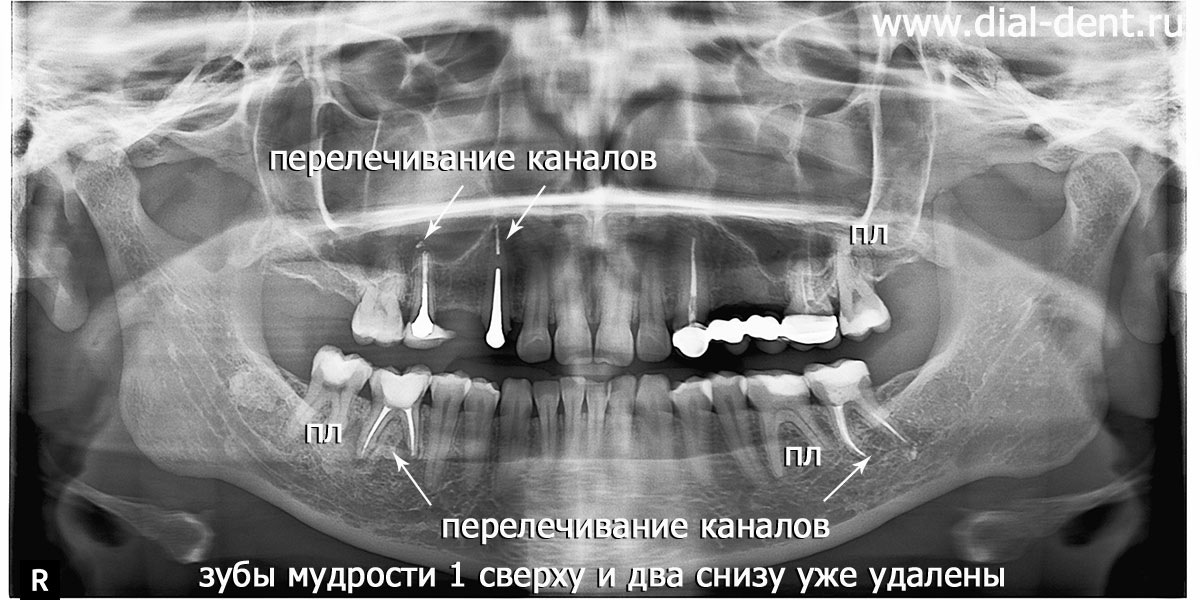

панорамный снимок зубов после удаления зубов мудрости и перед началом комплексного лечения

Проведя консультацию и изучив панорамный снимок зубов стоматолог-ортопед А.С. Иваньков предложил комплексно подойти к лечению - сначала пролечить проблемные зубы (перелечить каналы с микроскопом, вылечить кариес), удалить зубы мудрости, исправить прикус капами, установить импланты и на подготовленных зубах выполнить протезирование всех зубов керамическими коронками. Такое лечение даст долговечный результат.

2. Лечение кариеса в трех зубах, перелечивание каналов четырех зубов под микроскопом.

3. Удаление трех зубов мудрости по ортодонтическим показаниям до начала ортодонтического лечения.